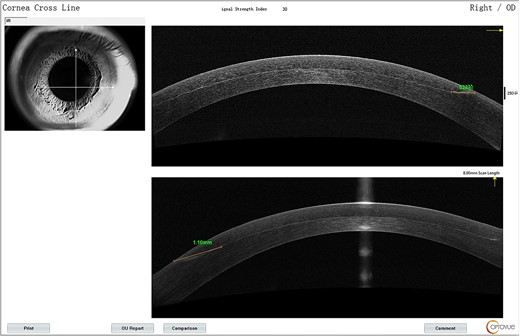

The lower part of the flap appeared grayish-white from Day 1.On AS-OCT, the lesion extent was 1.1 mm from the edge (Fig. 1) with reflectivity becoming higher. It was deemed as corneal edema and postoperative immunological response. The patient was prescribed fluorometholone 0.1% eye drops and 0.3% Ofloxacin eye drops for both eyes and asked to return in 5 days for reevaluation.

(A) AS-OCT signs for the right eye on the fifth day; (B) a detailed shot of the nasal inferior quadrant region.